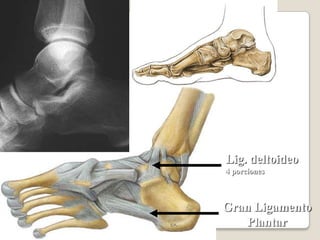

ARTICULACION TALOCURAL

sindesmosis tibioperoneaEs una articulacion fibrosa compuesta Es la union fibrosa que se establece entre la tibia y el perone por media de la membrana interosea (que une los cuerpos )NOTA:la integridad de la articulacion tibioperonea inferior es esencial para la estabilidadde la articulacion talocular ya que sostiene el maleolo lateral firmemente contra la cara lateral del astrago

Movimiento Se mueve ligeramente durante la flexion dorsal del pie como resultado del encaje de la troclea del astragalo entre los maleolos

Articulación tibioperoneaEs una articulación sinovial plana que se establece entre la cara articular plana de la cabeza del perone y una cara articular parecida que se localiza posterolateralmente en el condilo lateral de la tibia